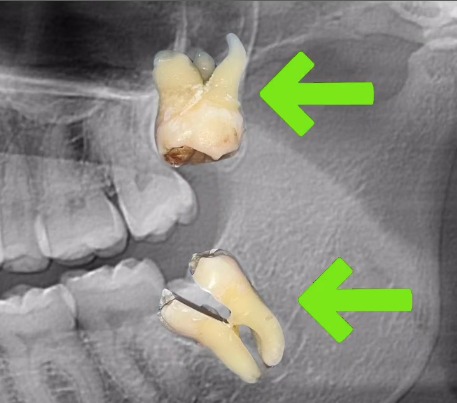

Casos de Endodoncia

En nuestras clínicas realizamos tratamientos de endodoncia con resultados comprobados, devolviendo la salud y funcionalidad a dientes afectados por caries profundas, traumatismos o infecciones. Cada paciente recibe un diagnóstico detallado, planificación personalizada y técnicas modernas que garantizan un tratamiento eficaz y cómodo.

Nuestros casos documentados muestran dientes tratados con éxito, preservando su estructura natural y restaurando la estética y la funcionalidad. Con endodoncia, evitamos extracciones innecesarias y ofrecemos soluciones duraderas que protegen tu sonrisa a largo plazo.